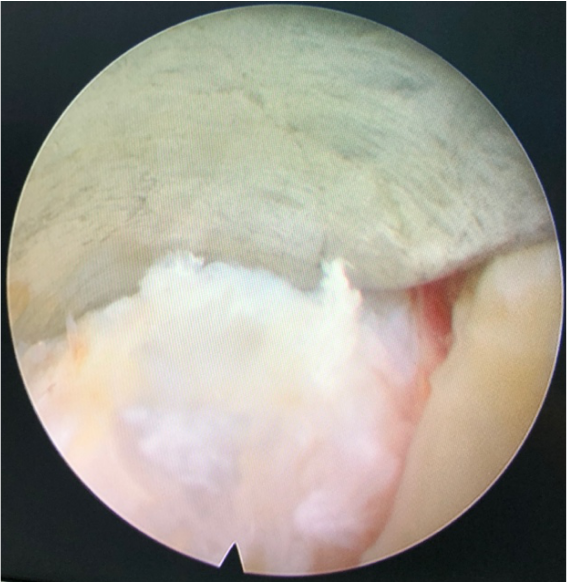

术中髓核突出,纤维环破裂

镜下神经根松解良好